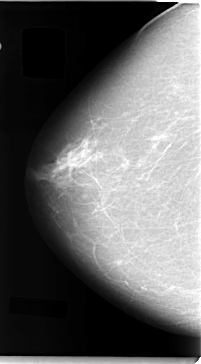

C_0040_1.RIGHT_CC

RIGHT_CC LINES 4728 PIXELS_PER_LINE 2608 BITS_PER_PIXEL 12 RESOLUTION 50 NON_OVERLAY